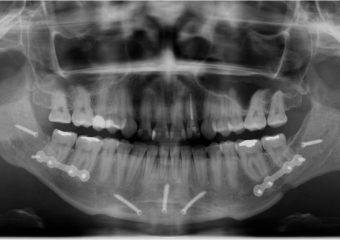

Raio x inicial